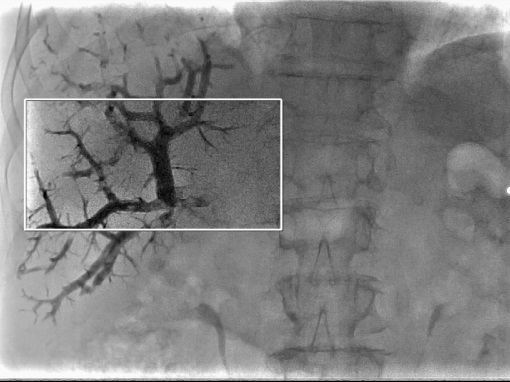

Режим Spot Fluoro

Режим Spot Fluoro передбачає асиметричну, сфокусовану на проблемній ділянці колімацію з одночасним відображенням оточуючої області та збереженням дози до 70%.

При цьому навколо ROI (область інтересу) знаходиться останнє збережене зображення (LIH). Таким чином знижується доза опромінення на пацієнта та розсіяне випромінювання на персонал, що буде особливо необхідним при довготривалих дослідженнях.